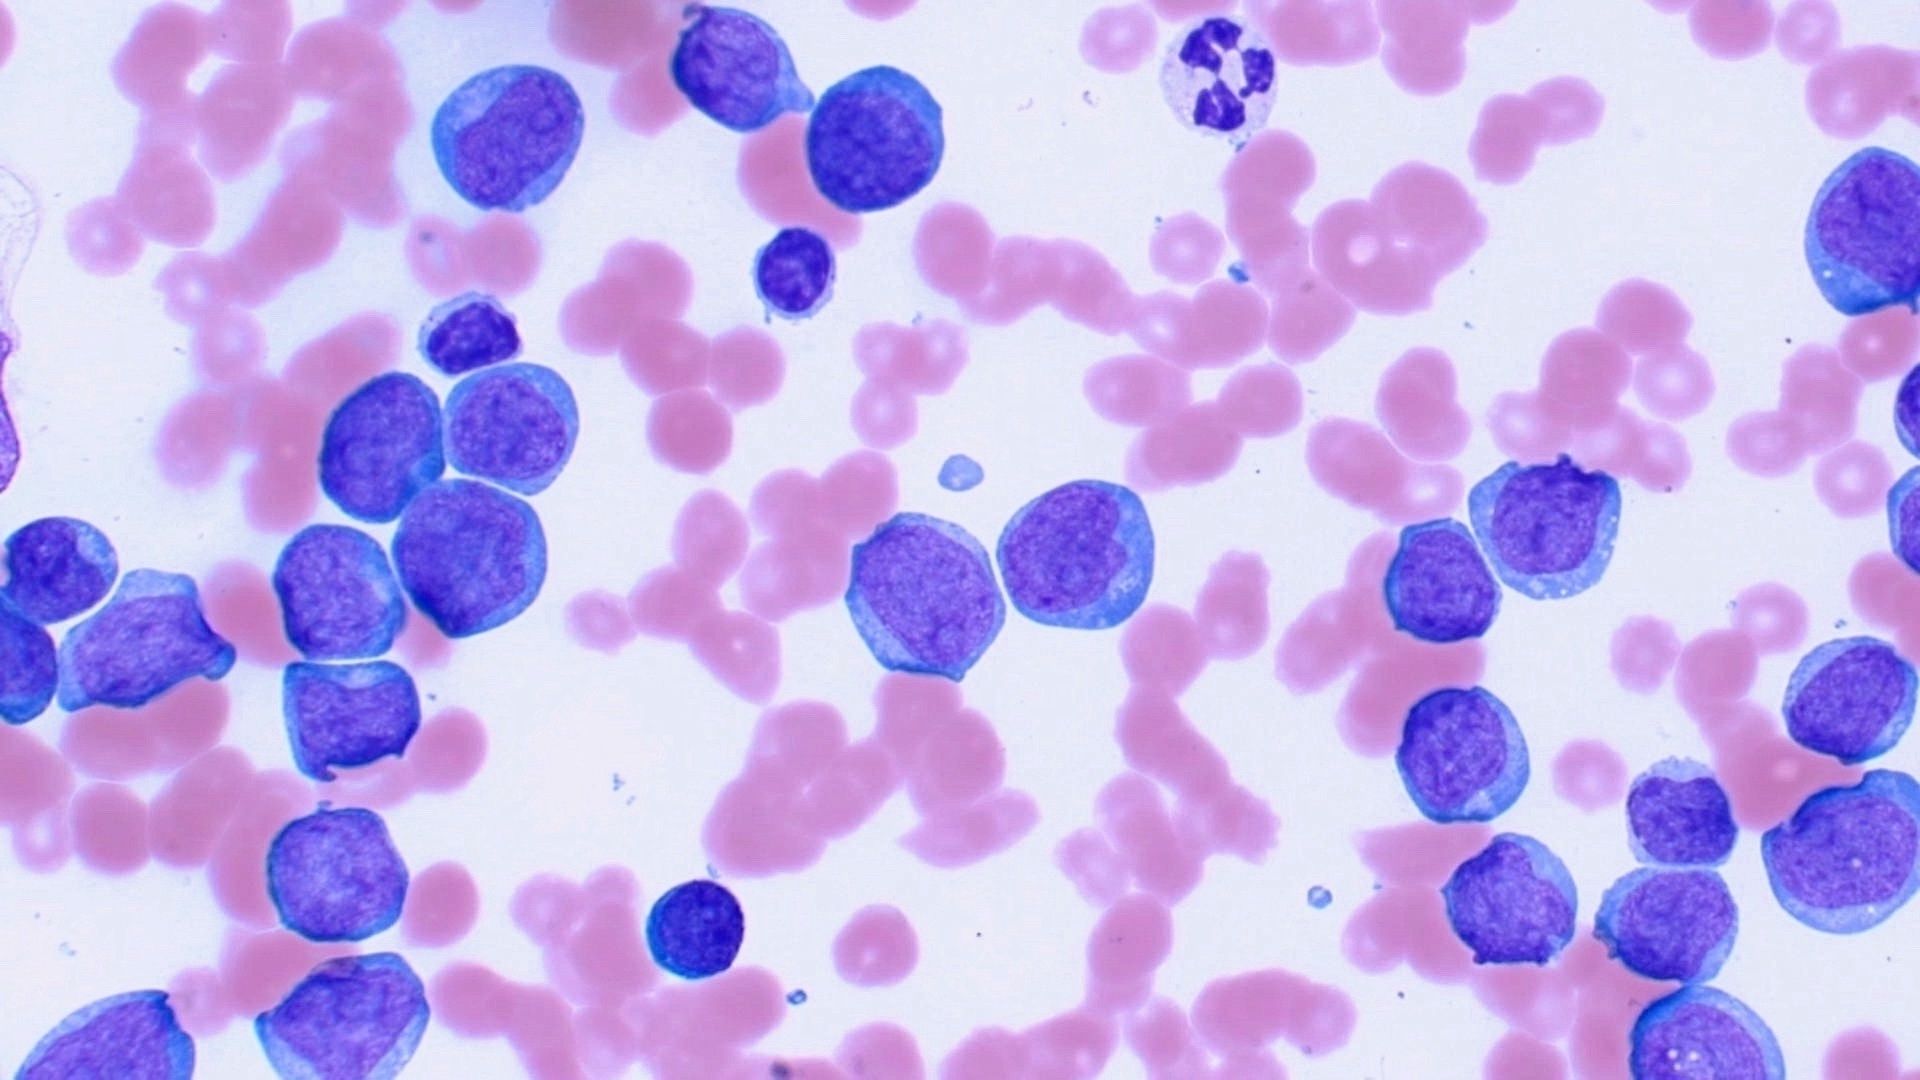

MASTERING CYTOLOGY: SKIN AND SUBCUTIS

Boost your confidence and skills in interpretation of fine-needle aspirate (FNA) cytology from masses/lesions in the skin and subcutis.

MASTERING HEMATOLOGY: PRACTICAL APPROACH TO CBC AND BLOOD SMEAR INTERPRETATION

Strengthen your identification skills and use that information in conjunction with the CBC to interpret what abnormalities mean for the patient.